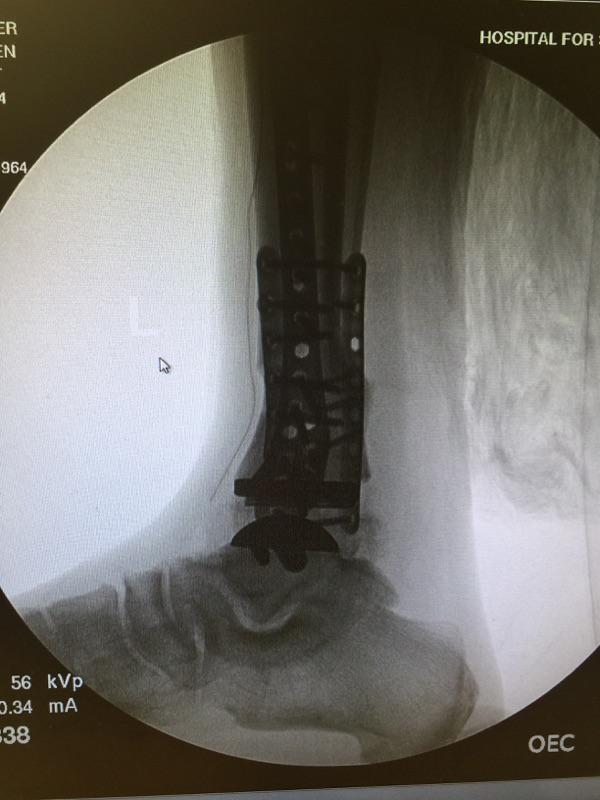

In January 2016, my life dramatically changed for the better thanks to the best HSS surgical team assembled to correct a severely painful, arthritic ankle and misaligned lower leg. Dr. Demetracopoulos is a highly skilled surgeon who performed a total ankle replacement (TAR) on my left ankle. In conjunction with the TAR, I was also the recipient of a much needed osteotomy to align my lower leg to the ankle implant so that my foot would point forward again and perfectly contact the ground in a level position to improve my gait.

Dr. Fragomen was a major contributor to these surgical procedures and I cannot thank him enough as well for helping. Just 3-1/2 years earlier in 2012, Dr. Fragomen performed a procedure on this same troubled ankle called arthrodiastasis in an attempt to allow my joint relief from bone-on-bone pain with distraction using external fixation for over 5 months. Unfortunately, arthrodiastasis only provided relatively short-term relief and some pain reduction. After a couple of years, my left ankle would again become painful and need a correction in the form of total reconstruction if I ever wanted long-term relief from pain and a return to a normal walking motion without a limp. Dr. Fragomen referred me to Dr. Demetracopoulos, the TAR specialist extraordinaire! Dr. "D" (easier to say) gave me my second opinion at HSS, since the first TAR surgeon with whom I consulted recommended two separate surgeries over the course of a year - first, to correct the lower leg alignment, then, after that healed, to do the ankle replacement. But then I visited Dr. D - he was like Superman to the rescue when he stated his confidence in accomplishing the same positive results performing both corrective procedures in ONE surgery! With one surgery I would only be subjected to one recovery period to heal from both procedures. I am blessed to have been introduced to such a miracle worker!